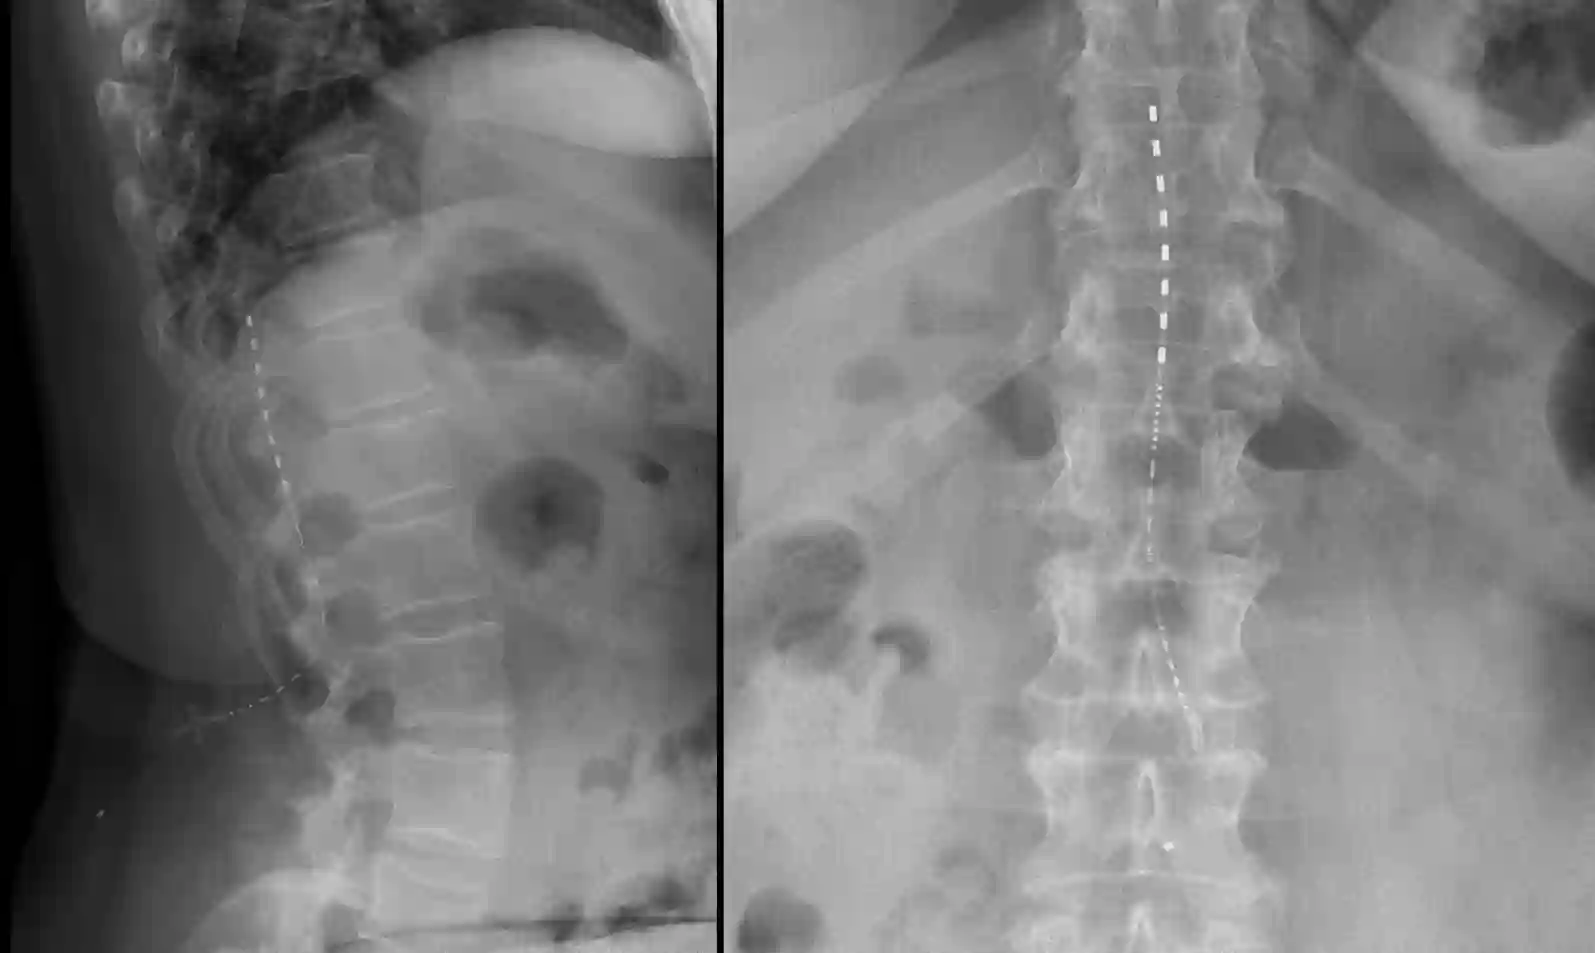

Stimwave Freedom-8A spinal cord stimulation (SCS)

Röntgenbild eines implantierten Wireless Stimwave Freedom-8A spinal cord stimulation (SCS) Systems.